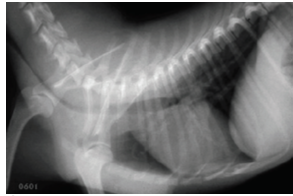

DCM